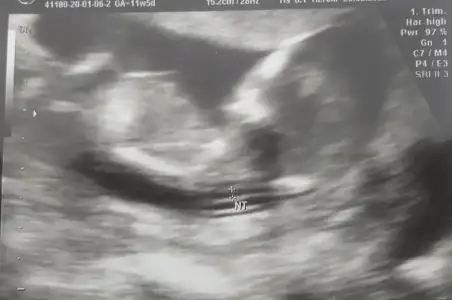

Banada bakarmısınız 12+2 günlükErkek ve kız için 11 yada 12 hafta usg görüntüsü olmalı açıklamalar asagıda yazıyorrabbim herkesin gönlüne göre nasip etsin inşallah .. ecmain

[/B]Eki Görüntüle 473828 gordugunuz gibi ust taraftaki simgedende anlasildigi gibi eger cikinti paralel ise kiz

yok 30°lik bir aciyla yukari dogru bakiyorsa %99 oglunuz olacak demektir simdi bi kac ornek resimler daha koyacagim kiziminkide dahil

yok 30 derecelik bir aciyla yukari bakiyorsa erkek

yabancilarin hepsi biliyor bunu biz neden eksik kalalim gayet bilimsel simdi ellerinde11 12 13 ultrason fotografi olanlar alsin hemen baksin yada koyalim buraya yorumlayalim